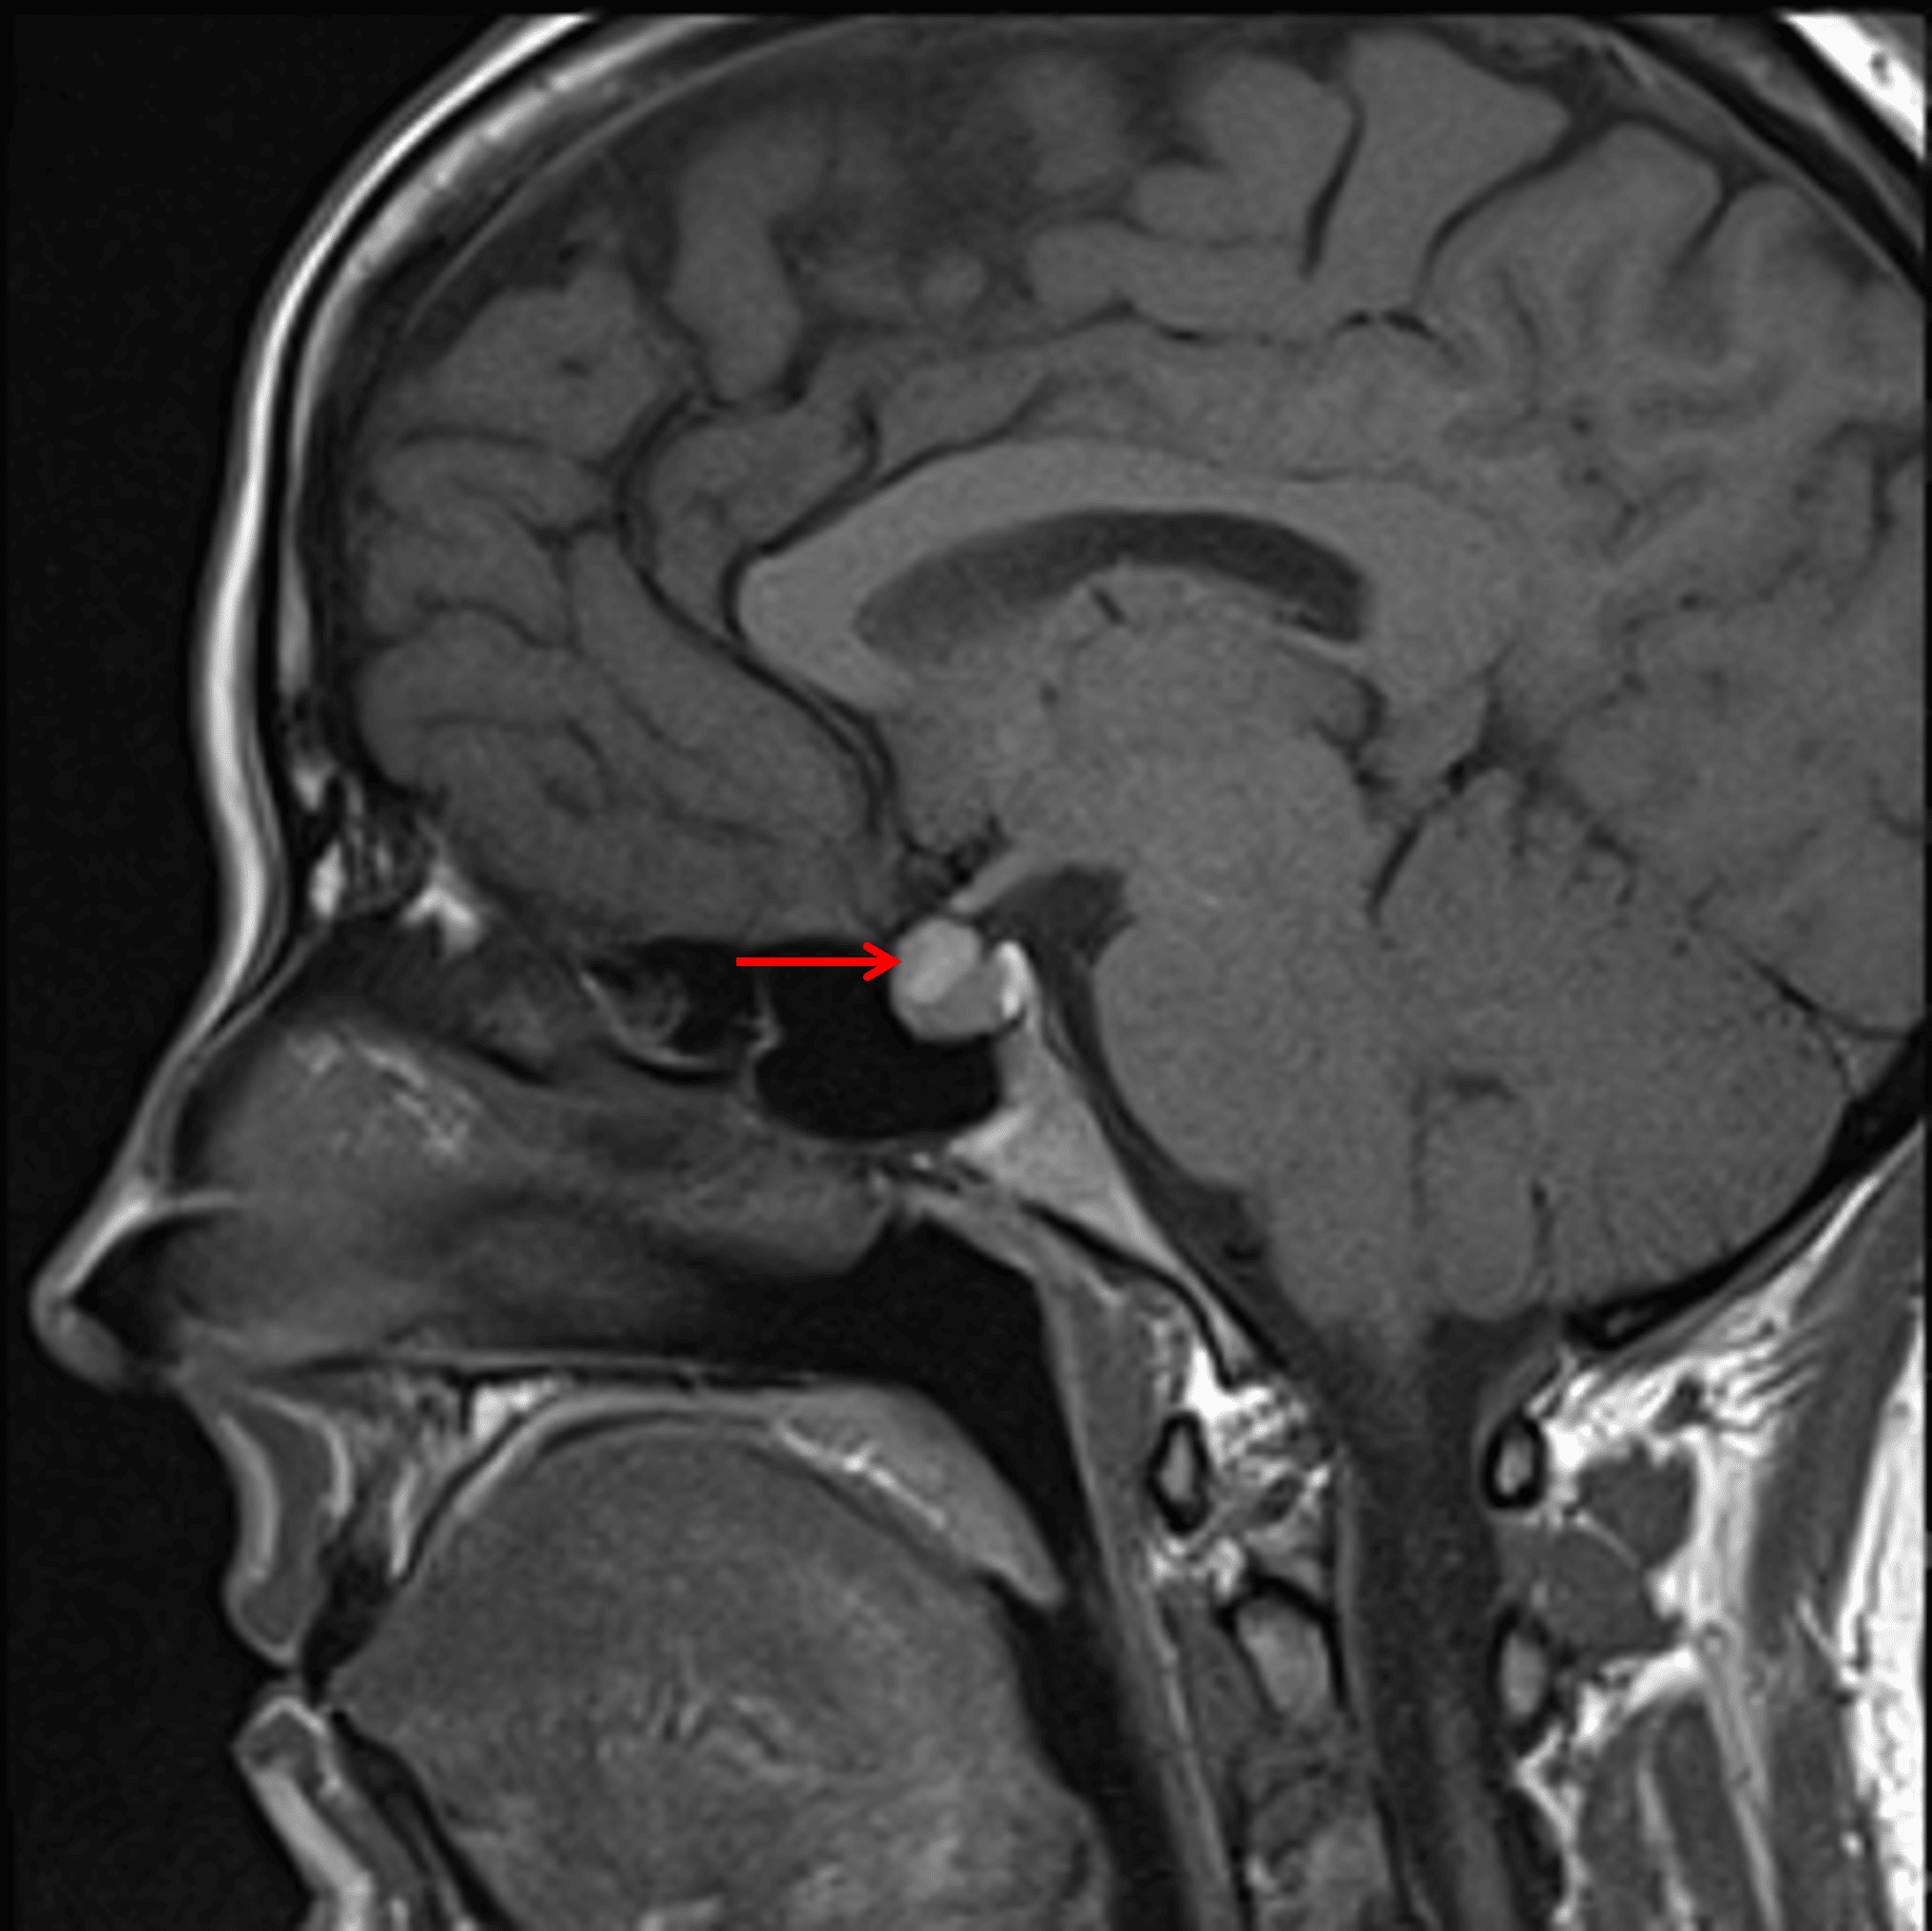

T1 hyperintense lesion along the superior margin of the pituitary gland (red arrow).

- T1 hyperintense, T2 isointense rounded lesion along the superior margin of the pituitary gland measuring 9 x 8 x 6 mm

- The lesion bulges into the suprasellar cistern but does not clearly contact the optic chiasm